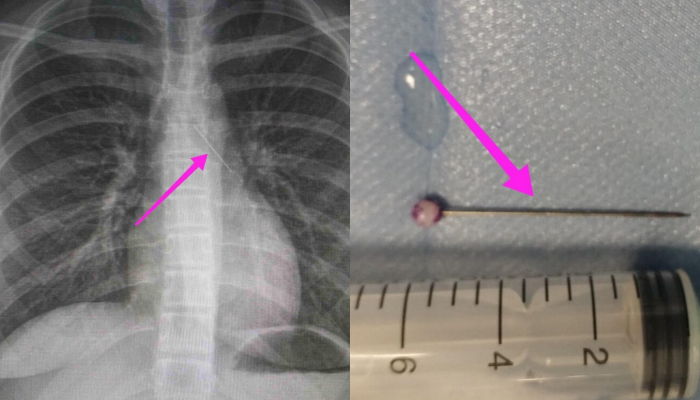

Η ανήλικη υπεβλήθη σε βρογχοσκόπηση και διαπιστώθηκε η μετακίνηση και ενσφήνωση της καρφίτσας στον δεξιό κύριο βρόγχο. Μετά οπό εργώδεις προσπάθειες ολοκληρώθηκε με επιτυχία η αφαίρεσή της.

Πραγματοποιήθηκε πλήρης προεγχειρητικός έλεγχος και RAPID PCR (COVID-19), και μετά την λήψη συγκατάθεσης των γονέων που συνόδευαν την ασθενή, οδηγήθηκε στη χειρουργική αίθουσα. Μετά από την χορήγηση γενικής αναισθησίας από την ιατρό Αναισθησιολόγο, Διευθύντρια κα Μαρία Μυλωνά (για την διεκπεραίωση του ιδιαίτερου αυτού περιστατικού) υποβλήθηκε σε βρογχοσκόπηση με άκαμπτο βρογχοσκόπιο από τους Ιατρούς Ω.Ρ.Λ., Καρασμάνη Ηλία και Μαγγανάρη Αργύρη, Επιμ Α’ της ΩΡΛ Κλινικής του Γ.Ν.Θ. «Ιπποκράτειο».

Κατά την βρογχοσκόπηση διαπιστώθηκε η μετακίνηση και ενσφήνωση του ξένου σώματος στον δεξιό κύριο βρόγχο. Μετά από εργώδεις προσπάθειες ολοκληρώθηκε με επιτυχία η αφαίρεση αυτού. Η ασθενής ανένηψε πλήρως εντός της χειρουργικής αίθουσας. Η ασθενής μεταφέρθηκε για παρακολούθηση και νοσηλεία στη Γ’ Παιδιατρική Κλινική.